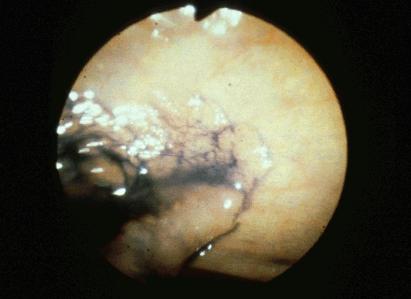

部位(臓器別)大腸/直腸

検査方法内視鏡

病変の最大径(ミリ)40以上